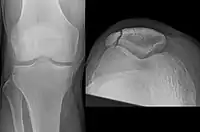

Patella fracture

A fracture of the patella seen on a lateral view